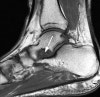

MRI : 후경골근 장애(Posterior tibial tendon dysfunction, PTTD)